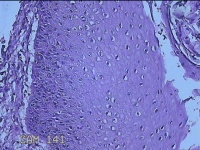

剑突下结节

性别

女

年龄

26岁

临床诊断

皮下结节

一般病史

发生剑突下结节1年余,无明显疼痛及不适。

标本名称

大体所见

灰白暗红色组织2x1.8x1.3cm一个,表面带梭形皮肤1.8x0.8cm,皮下见结节2.2x2x0.7cm一个,切开结节呈实性,切面灰白暗红色,质软。